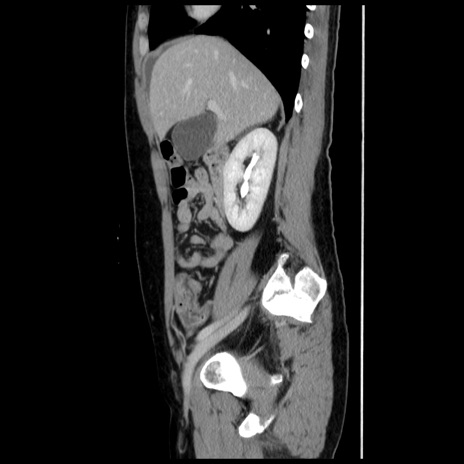

横断像

【症例】 50歳代女性

【主訴】 腹痛

【現病歴】前日生レバーを食べた。今朝に排便あり。 昼前に突然発症の腹痛を生じ、当院救急外来を受診した。

【既往歴】 子宮筋腫にてで子宮全摘後

【身体所見】 意識清明、腹部:平坦、軟、下腹部やや左を中心に圧痛・反跳痛あり、筋性防御あり

【データ】WBC 7800、CRP 0.07